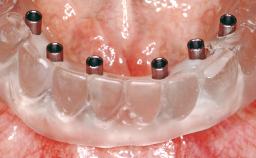

A 63-year-old male patient was referred for a consultation and treatment of partial edentulism in the maxilla. The patient presented with residual anterior teeth and declined a partial removable prosthesis. He reported that the maxillary posterior teeth had been extracted due to mobility and periodontal disease two months before the consultation. The patient’s chief complaint was that his residual maxillary teeth were mobile and that he was unable to chew. The patient’s desire was a stable and comfortable fixed maxillary rehabilitation. The patient was a light smoker (fewer than 10 cigarettes/ day), and his medical history was without significant findings. He was not on any regular medication at the time of consultation. The extraoral examination revealed a normal physiognomy with a correct distribution of the facial thirds. The patient presented a low lip line, and the transition line between teeth and soft tissues was not exposed during a forced smile.

# of Implants 6

Type of Implants One-Piece

Modality 6+ implants with immediate loading